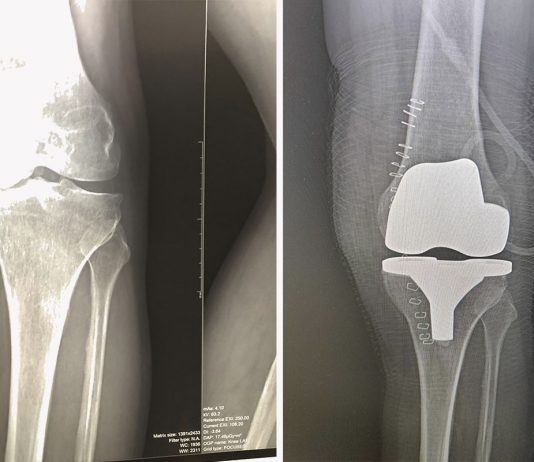

Эндопротезирование коленного сустава – распространенная операция в травматологии, ортопедии и спортивной медицине. Установка импланта из прочных гипоаллергенных материалов решает ряд необратимых изменений, возникших при заболеваниях опорно-двигательного аппарата. Об услугах и клинике протезирования можно узнать, перейдя по ссылке https://medicalplaza.ua/content/endoprotezirovanie-kolennogo-sustava.

Протез коленного сустава помогает вернуться к активной жизни без боли и дискомфорта....